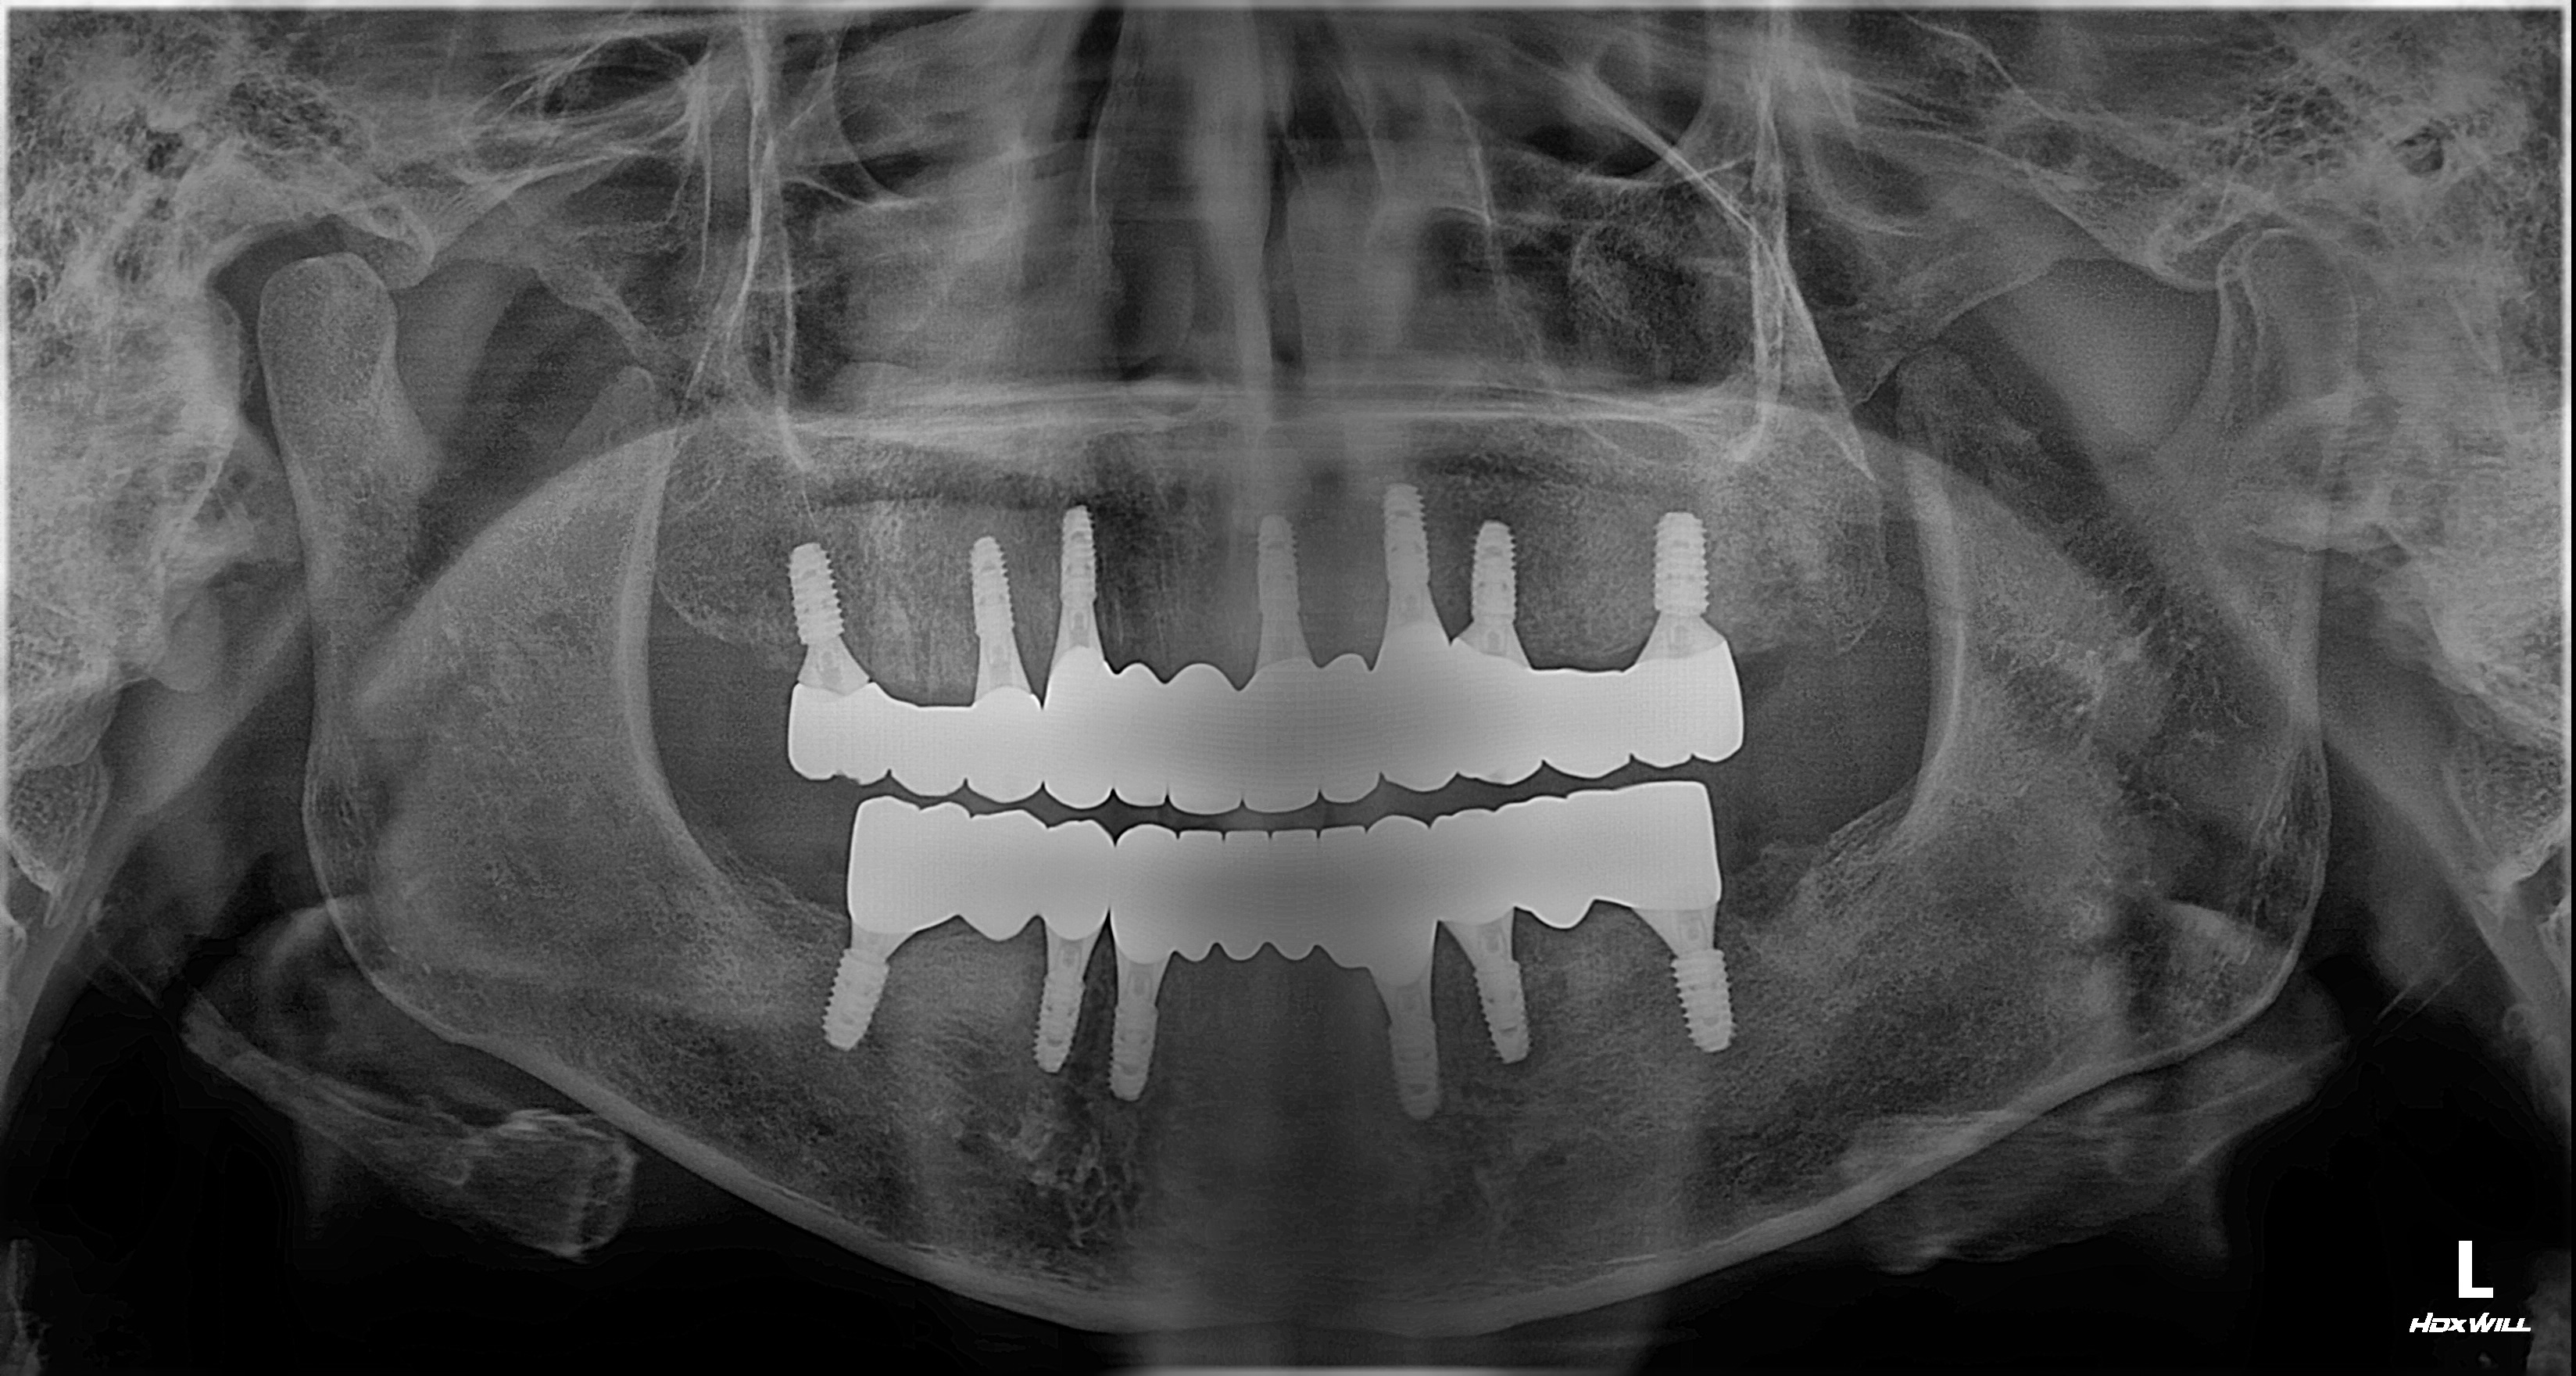

촬영일시: 2025.05.27

촬영일시: 2025.10.01 [ 치료기간: 2025년 05월 27일 ~2025년 10월 01일 ] ※ 365서울앞선치과의원의 모든 컬럼은 각 진료과 의료진이 직접 작성합니다. 365서울앞선치과의원 임상 케이스 게시물은 환자분께 의학적으로 정확하고 상세한 정보를 드리기 위해 각 진료과 의료진이 직접 작성하며, 모든 증례 사진은 본원 의료진이 직접 시술한 증례를 촬영한 것으로, 의료법 제23조, 제56조에 의거하며 환자분의 동의를 얻어 포스팅에 사용하였습니다. 또한 해당 케이스는 본 환자분의 치료 결과이며, 환자 상태에 따라 치료의 결과는 달라질 수 있습니다. |